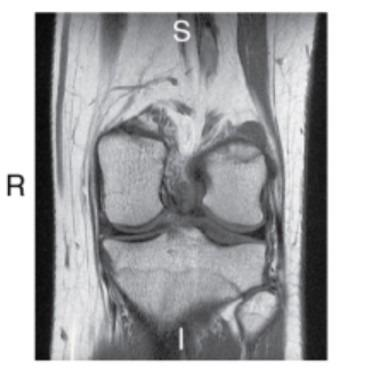

What imaging plane is this?

coronal